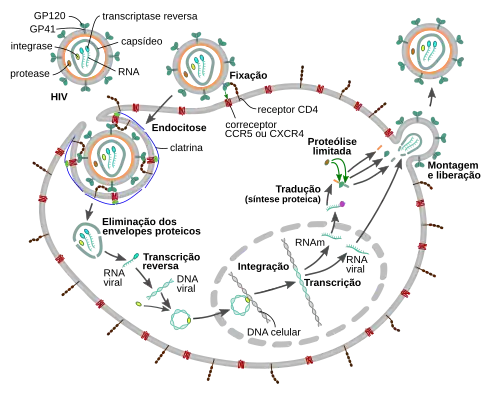

Ciclo de replicação

Penetração celular

O VIH penetra nos macrófagos e nos linfócitos T CD4+ através da adsorção de glicoproteínas na sua superfície para recetores na célula-alvo, seguida pela fusão do envelope viral com a membrana celular e pela libertação do capsídeo do VIH na célula.[46][47]

A penetração na célula tem início com a interação do complexo envelope trímero (gp160) com o CD4 e um recetor de quimiocina na superfície da célula (geralmente o CCR5 ou CXCR4, embora sejam conhecidos outros).[46][47] A gp120 liga-se à integrina α4β7, ativando o LFA-1, a principal integrina envolvida no estabelecimento de sinapses virológicas, que facilita a disseminação eficiente do VIH-1 entre células.[48] A gp160 contém domínios de ligação tanto para o CD4 como para os recetores de quimioquina.[46][47]

O primeiro estágio na fusão envolve a união dos domínios de ligação CD4 da gp120 ao CD4. Isto decorre normalmente nos limites dos domínios lipídicos onde tanto o recetor CD4 como os recetores CCR5 e CXCR4 têm uma maior probabilidade de estar próximos[49]. Uma vez ligada a gp120 com a proteína CD4, o complexo envelope atravessa uma alteração na estrutura, expondo os domínios de ligação de quimioquina da gp120 e permitindo-lhes interagir com o recetor-alvo de quimioquina, CCR5 ou CXCR4, que são os coreceptores do VIH.[46][47] Isto permite uma ligação mais estável, o que permite ao peptídeo de fusão N-terminal gp41 penetrar na membrana celular.[46][47] Em seguida, as sequências de repetição na gp41, HR1 e HR2 interagem entre si, provocando o colapso da porção extracelular da gp41 num hairpin. Esta estrutura circular aproxima o vírus da membrana celular, permitindo a fusão das suas membranas e consequente entrada do capsídeo viral.[46][47]

Depois do VIH se ligar à célula-alvo, injeta nela o seu ARN e as suas diversas enzimas, incluindo a transcriptase reversa, integrase, ribonuclease e protease.[46] O VIH pode infetar células dendríticas (CD) através do processo CD4-CCR5, embora possa também usar recetores de lectina tipo C.[50] As células dendríticas são uma das primeiras células que o vírus encontra durante a transmissão por via sexual. Atualmente, pensa-se que as CD desempenhem um papel importante na transmissão do VIH para os linfócitos, durante o momento em que o vírus é capturado na mucosa.[50] Acredita-se que a presença da proteína FEZ-1, que ocorre naturalmente em neurónios, impeça que o VIH infecte as células.[51]

Replicação e transcrição

Pouco depois do capsídeo viral penetrar na célula, uma enzima denominada transcriptase reversa liberta o genoma ARN de cadeia única das proteínas virais, e copia-o para uma molécula complementar de ADN.[52] O processo de transcrição reversa é extremamente predisposto a erros e as mutações daí resultantes podem provocar resistência aos anti-virais ou permitir ao vírus evadir o sistema imunitário. A transcriptase reversa tem também atividade de ribonuclease, que degrada o ARN viral durante a síntese de ADN complementar, assim como atividade de ADN polimerase ADN-dependente, capaz de criar ADN de sentido positivo a partir do ADN complementar de sentido negativo.[53] Juntos, o ADN complementar e o seu complemento forma um ADN viral de cadeia dupla que é assim transportado para o núcleo celular. A integração do ADN viral com o genoma das células anfitriãs é realizada por outra enzima viral, denominada integrase.[52]

O ADN viral, agora integrado na célula, pode permanecer dormente durante a fase latente da infeção.[52] De forma ao vírus poder ser produzido de forma ativa, têm que estar presentes determinados fatores de transcrição, o mais importante dos quais o NF-κB (factor nuclear kappa B), que é depois supra-regulado quando os linfócitos T são ativados.[54]

Durante a replicação viral, o AND proviral integrado é transcrito para ARNm, que é depois reorganizado através de splicing em partes mais pequenas. Estas partes são exportadas do núcleo para o citoplasma, onde são transcritas para as proteínas reguladoras Tat (que incentiva a produção de novos vírus) e Rev. À medida que as proteínas Rev recém-formadas se acumulam no núcleo, vão-se ligando ao ARNm viral e permitem ao ARN que ainda não sofreu splicing abandonar o núcleo, onde de outra forma são retidos até sofrerem splicing.[55]

Montagem e lançamento

O último passo do ciclo viral, a montagem dos viriões do novo VIH-1, tem início na membrana de plasma da célula anfitriã. A poliproteína Env (gp160) atravessa o retículo endoplasmático e é transportada para o complexo de Golgi, onde é dividida pela furina, dando origem às duas glicoproteínas do envelope do VIH, gp41 e gp120.[63] Estas proteínas são transportadas para a membrana plasmática da célula anfitriã, na qual a gp41 fixa a gp120 à membrana da célula infetada. As poliproteínas Gag (p55) e Gag-Pol (p160) também interagem com a superfície interior da membrana plasmática, em conjunto com o ARN genómico do VIH, à medida que o virião em formação começa a despontar da célula anfitriã. Este novo virião encontra-se ainda imaturo, uma vez que as poliproteínas Gag precisam ainda de ser separadas em proteínas de matriz, capsídeo e nucleocapsídeo. Esta divisão é mediada pela protease viral e pode ser inibida por fármacos antirretrovirais da classe dos inibidores da protease. Finalmente, os vários componentes são montados de modo a produzir um virião de VIH amadurecido, que são os únicos capazes de infetar outras células.[64]